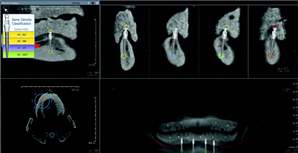

3-D software can shade images to differentiate varying densities of facial structures. Grayscale shading provides the ability to view the relationships of common internal anatomy. Traditional CT imaging renders an 8-bit grayscale (256 shades) or 12-bit grayscale (4,096 shades). Present-day scanners render images in 14-bit grayscale, providing 16,384 shades. Color coding the image by density further distinguishes anatomical structures, enabling the clinician to view pertinent anatomy while planning implant cases, such as nerves and nasal cavities, and mandibular and maxillary dimensions. Segmentation literally cuts the volume rendering, conceding top views, side views, and CT slices that produce unlimited axial, coronal and sagittal views. CBCT slices are as thin as 0.1 mm, compared to 1 mm for a conventional fan CT scan.

CBCT imaging is the ideal radiological modality for implantology due to the high quality of the produced images, software capabilities, and lower doses of radiation exposure. Two of the hottest topics regarding CBCT and implantology are virtual surgery planning and surgical guides. A virtual surgery can be performed with special software applications that enable dentists to evaluate the quality of bone through density shading and dimensions of bone can be recorded accurately with 1:1 measurement tools. It identifies common internal anatomy needed to evaluate implant placement including the jaw boundaries, adjacent teeth, nasal fossa, mandibular canal, maxillary sinus, mental foramen, and incisive canal. It also detects pathology to be avoided for implant health. Therefore, before the surgery, the clinician can confirm the appropriate implant size, location and angulation, and that plan can be fed to a 3-D printer to produce a surgical guide or stent for use during the actual surgery.